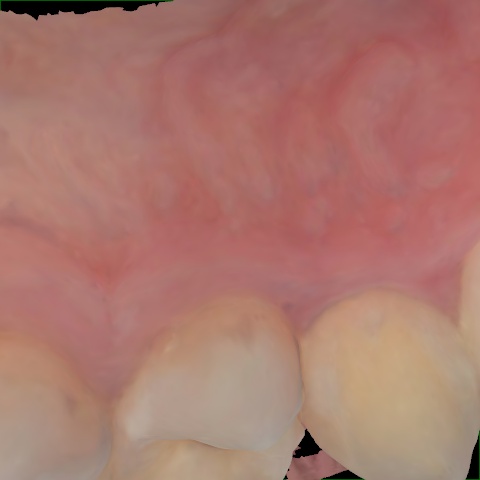

Annotated as "Good"